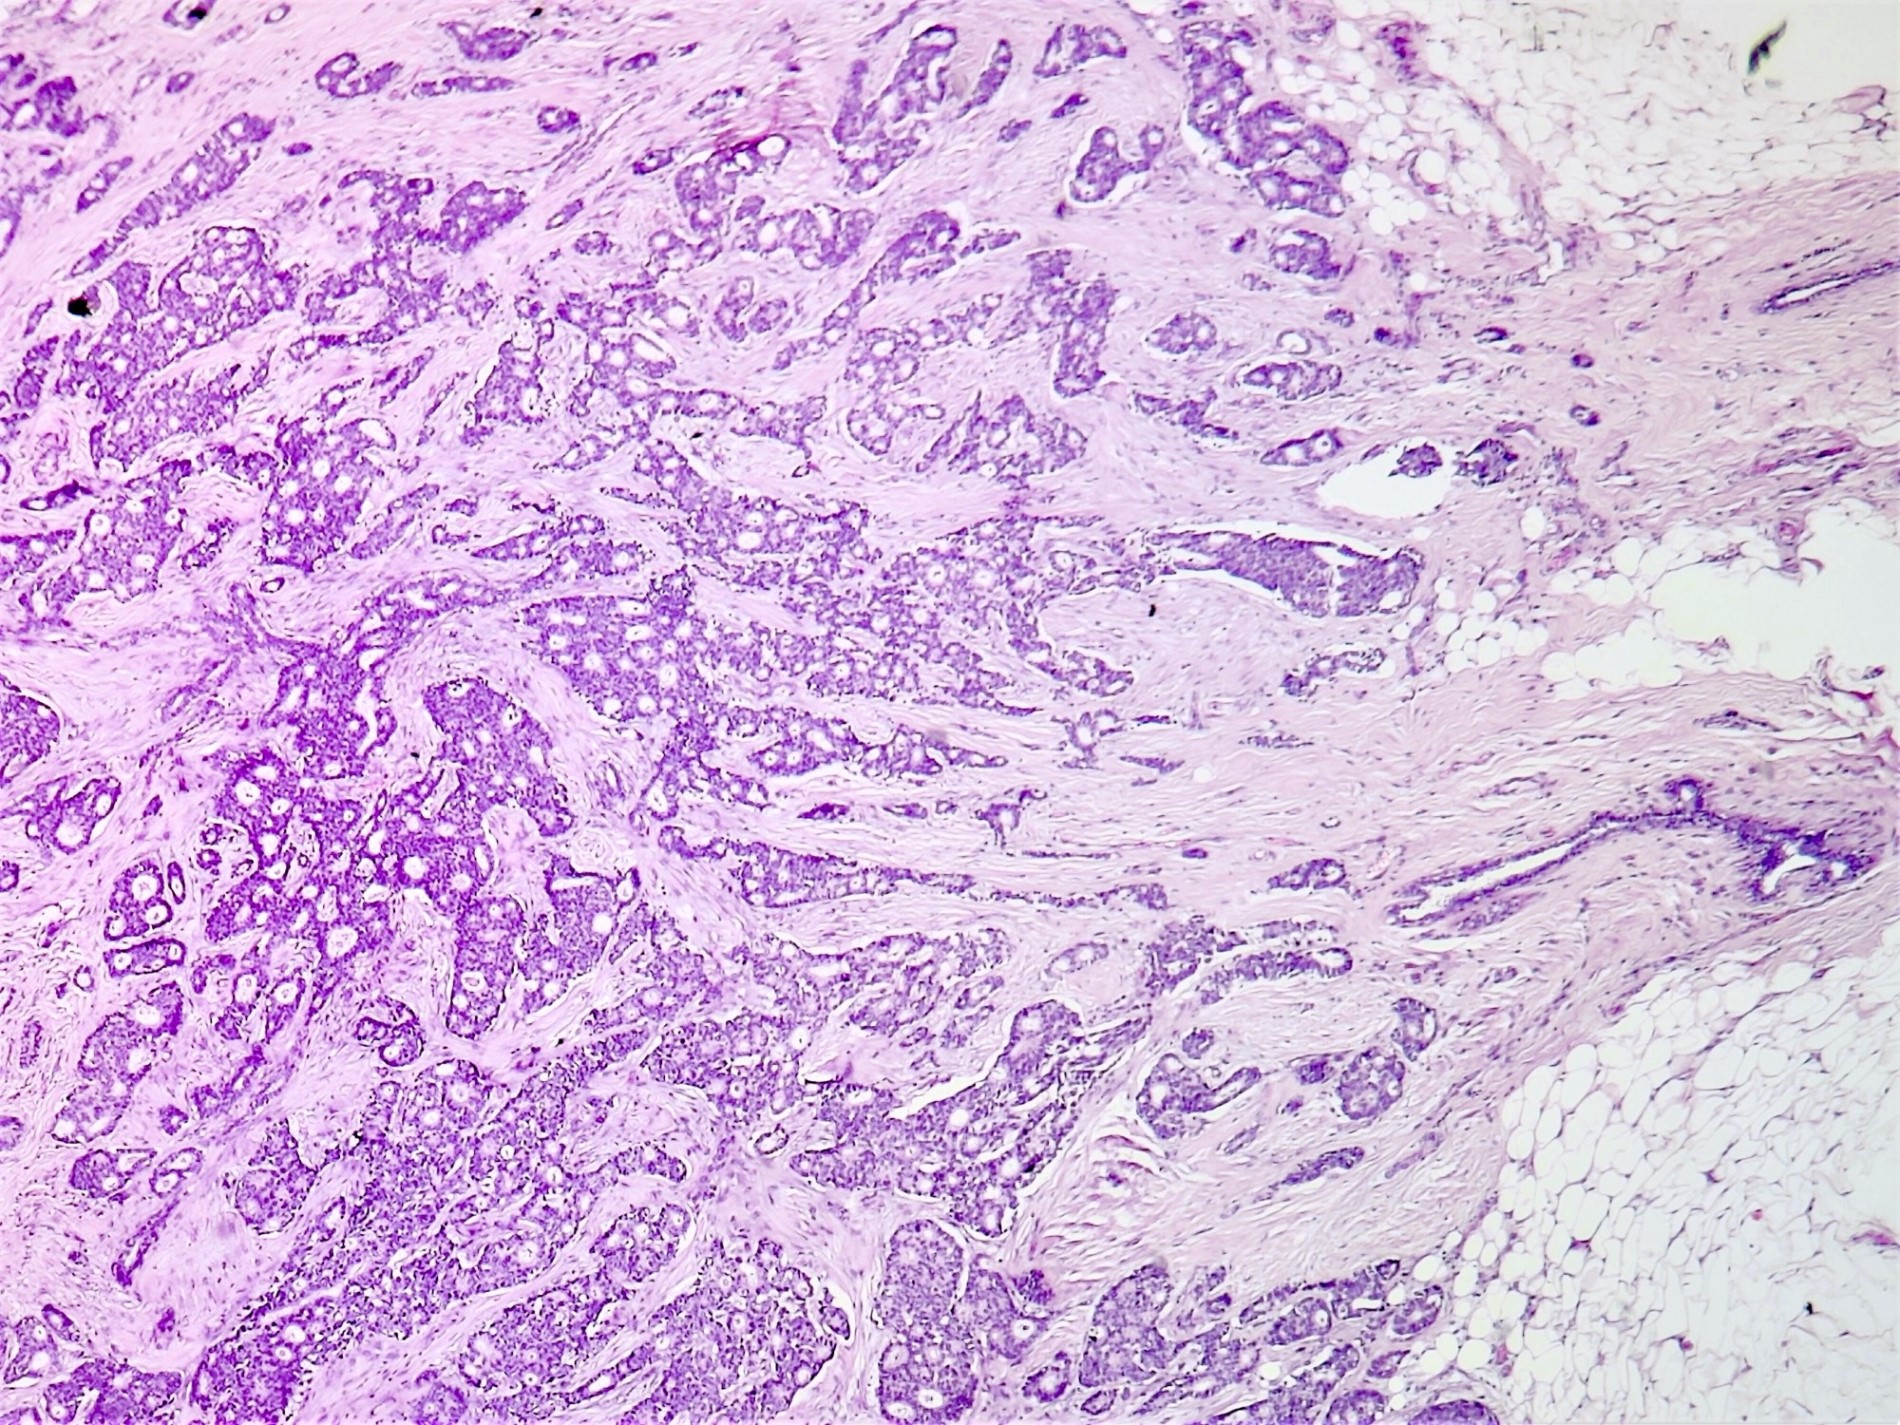

Microscopic (histologic) description

- Irregular cribriform growth pattern > 90% of cells

- Nuclear grade I pure ICC: > 90% cribriform pattern

- Mixed: 10 - 90% other morphological type, other than cribriform carcinoma

- Low grade: Nottingham grade 1 tumors

- Invasive islands or nests of malignant cells with round or angulated contours and well defined cribriform spaces formed by arches of epithelial cells; this gives a sieve-like appearance

- Tumor cells: small, mild / moderate pleomorphism, no nuclear atypia

- No / sparse mitotic activity

- Desmoplastic stroma

- Mucin positive secretion, microcalcifications in lumen

- Osteoclastic giant cells may be seen

- Myoepithelial cells absent

- Associated with cribriform ductal carcinoma in situ (DCIS)

Microscopic (histologic) images

Contributed by Sunitha Shankaralingappa, M.B.B.S, M.D., D.M.